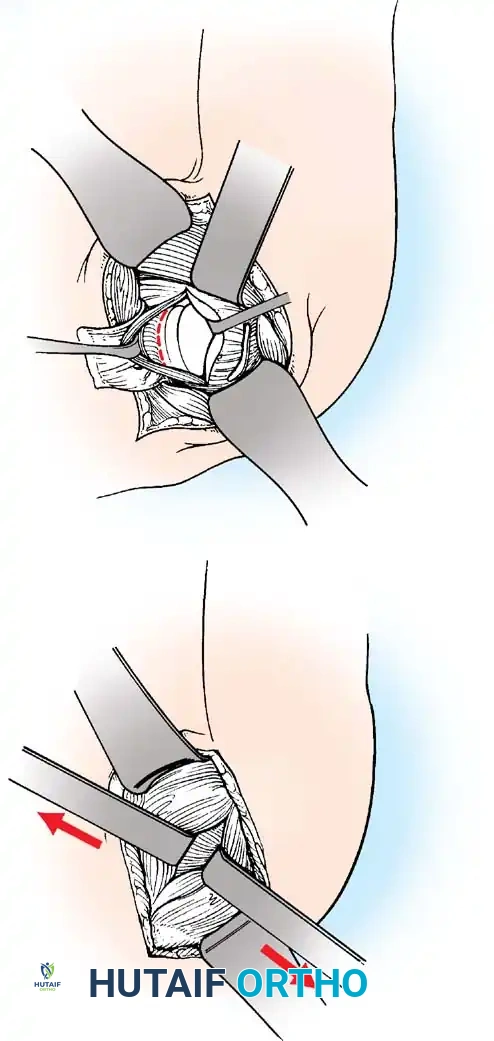

Glenoid Preparation and Labral Repair

The essential step in restoring stability is the anatomical reduction of the capsulolabral complex to a bleeding bone bed on the anterior glenoid rim.

- Debridement: The anterior glenoid neck is decorticated using a motorized burr, rasp, or osteotome to create a bleeding cancellous bed. This promotes robust biological healing of the repaired labrum.

- Mobilization: The scarred, medially displaced labrum (ALPSA lesion) must be fully mobilized using a periosteal elevator until the subscapularis muscle belly is visible anteriorly. The tissue must float freely to be shifted superiorly and laterally.

- Anchor Placement: Suture anchors (typically 3 to 4) are placed along the articular margin of the anteroinferior glenoid (from the 5:30 to 3:00 positions for a right shoulder). Anchors must be inserted at a 45-degree angle to the articular surface to maximize pullout strength and avoid joint penetration.